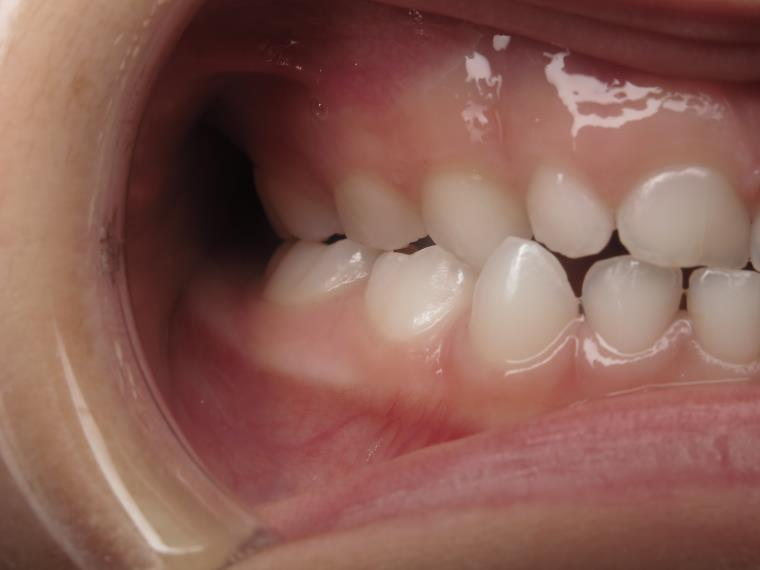

surveillance évolution de la dentition en cours

bilan début et en cours de traitement